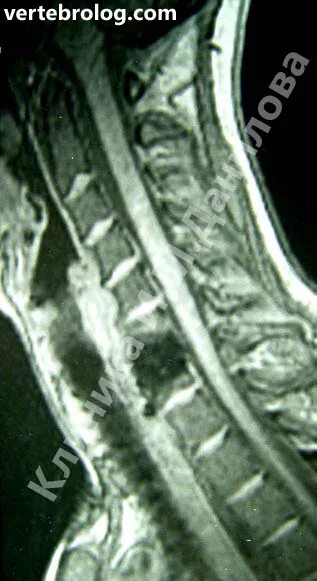

Протрузии дисков c6